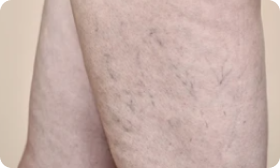

Arañas vasculares: pintura corporal que no tenías prevista

Estos "patrones" no embellecen tus piernas.

Después de mi segundo parto, de repente noté venas en la parte inferior de los muslos que parecían telarañas rojas.

Eran demasiado visibles, así que tenía que ocultar esa "telaraña" debajo de faldas y vestidos largos.

Incluso hace 2 meses mis piernas parecían como si una araña enorme viviera dentro de ellas y tejiera su telaraña cada día. Año tras año las arañas vasculares crecían y me entristecían.